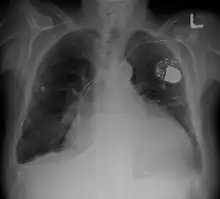

Cardiomegaly on chest X-ray with a pacemaker

• Chest X-ray: X-ray images help to visualize the condition of the lungs and heart. If the heart is enlarged on an X-ray, other tests will usually be needed to find the cause. A useful measurement on X-ray is the cardio-thoracic ratio, which is the transverse diameter of the heart, compared with that of the thoracic cage.[24] These diameters are taken from PA chest x-rays using the widest point of the chest and measuring as far as the lung pleura, rather than lateral skin margins. If the ratio is greater than 50%, pathology is suspected.[25] The measurement was first proposed in 1919 to screen military recruits. A newer approach to using these x-rays for evaluating heart health takes the ratio of heart area to chest area and has been called the two-dimensional cardiothoracic ratio.[26]